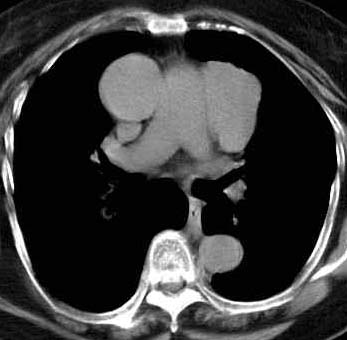

CaseKS08

Case B

あなたの診断はWhat is your first impression?